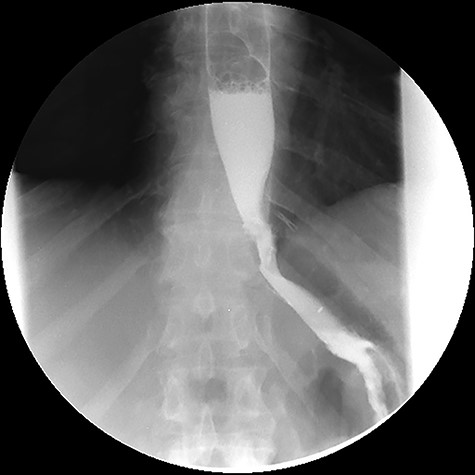

A last endoscopic treatment attempt of the oesophageal fistula was made 8 weeks after hospital discharge (October 2015), whereby a covered biodegradable stent was used and stabilized in place with clips (see Fig. 6). The success of the last endoscopic approach was confirmed with upper GI contrast swallow study (see Fig. 7). Oral feeding was reintroduced with tolerance.

Upper gastrointestinal contrast swallow study image where is possible to see normal progression of contrast from the oesophagus to the stomach without leaks.